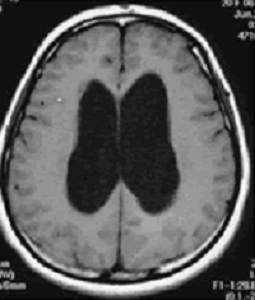

水頭症 慶應義塾大学病院脳神経外科教室

水頭症 その1 脳卒中をやっつけろ

水頭症の特徴と症状

Inphの原因 高齢者の水頭症 Inph Jp